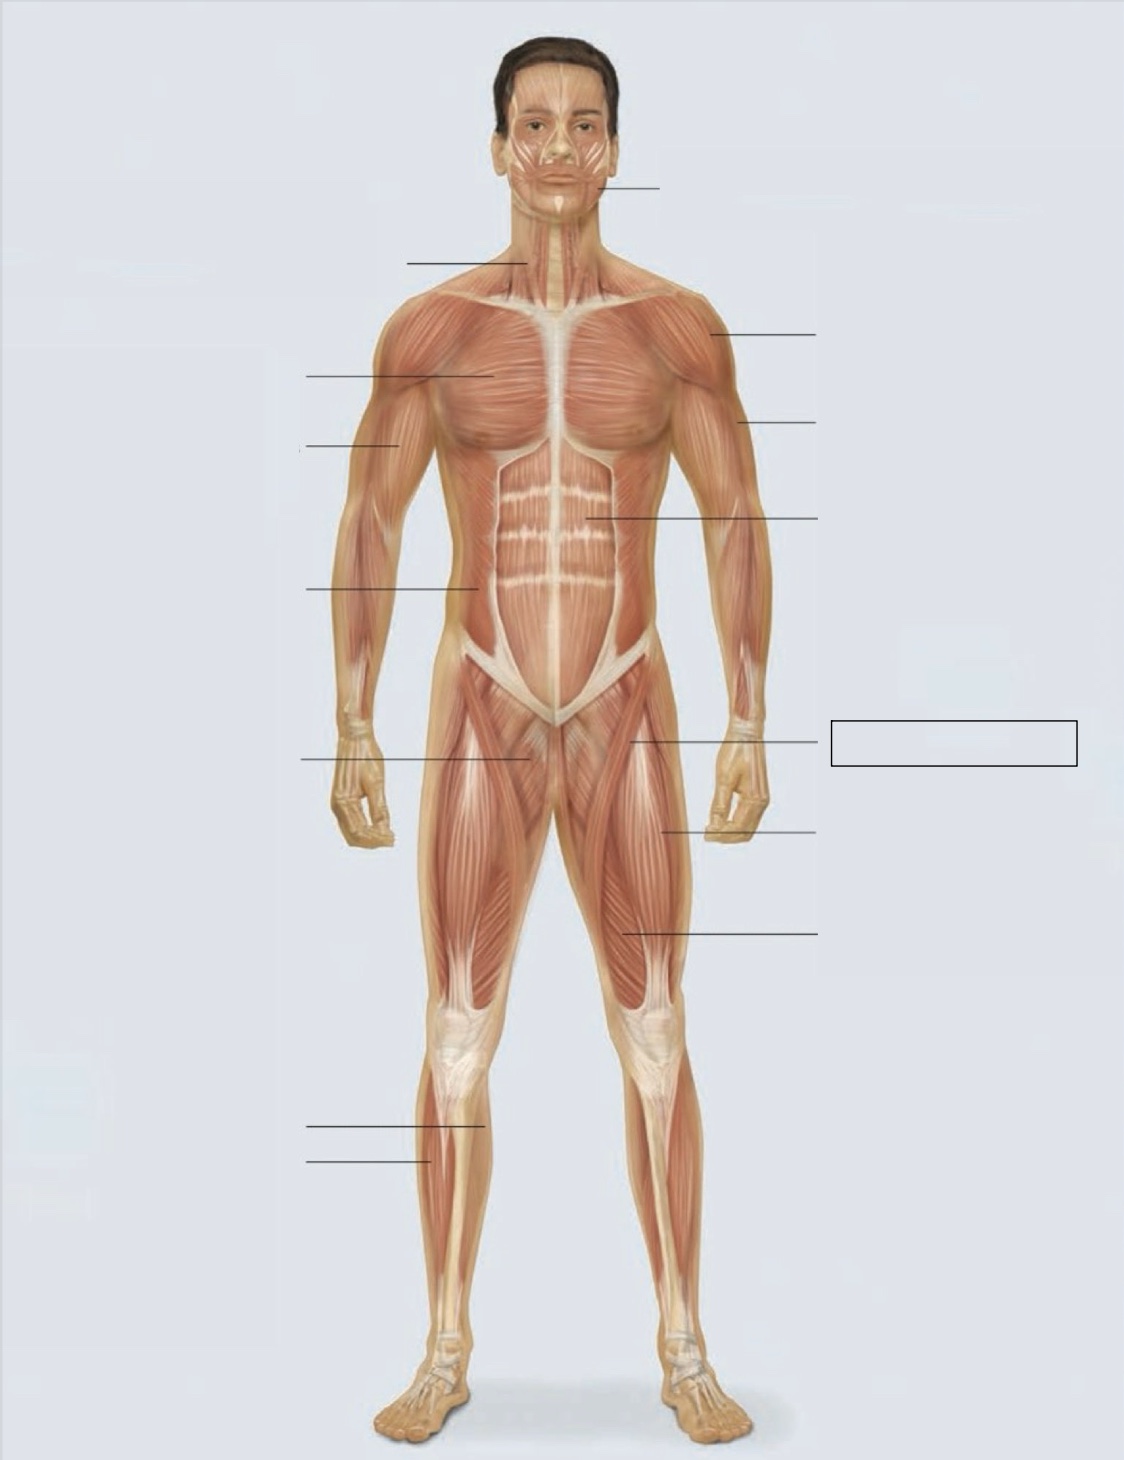

masseter

deltoid

triceps

rectus abdominis

sartorius

quadriceps femoris